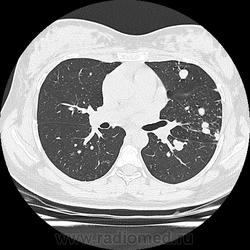

- https://radiomed.ru/sites/default/files/styles/case_slider_image/public/user/19376/img-0001-00042.jpg?itok=2lfc8wWs

- https://radiomed.ru/sites/default/files/styles/case_slider_image/public/user/19376/img-0001-00052.jpg?itok=YRoMhMgw

- https://radiomed.ru/sites/default/files/styles/case_slider_image/public/user/19376/img-0001-00056_0.jpg?itok=nxleffCp

- https://radiomed.ru/sites/default/files/styles/case_slider_image/public/user/19376/img-0001-00061.jpg?itok=rsGqsfJo

- https://radiomed.ru/sites/default/files/styles/case_slider_image/public/user/19376/img-0001-00066.jpg?itok=jCurkizB